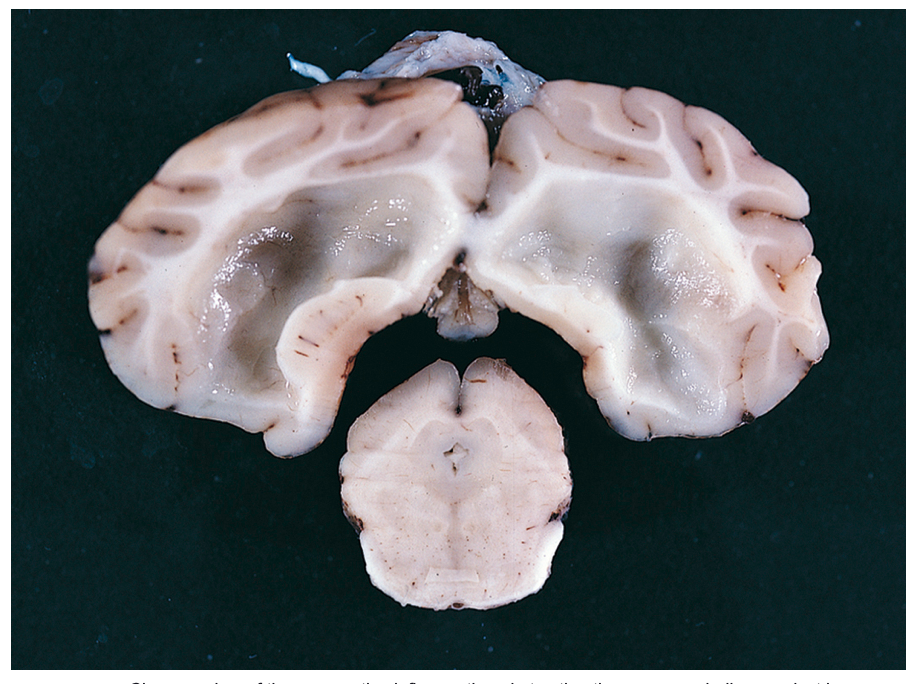

Transverse sections of the brain of a 5-year-old golden retriever showing a dilated left lateral ventricle caused by a choroid plexus papilloma obstructing the left interventricular foramen.